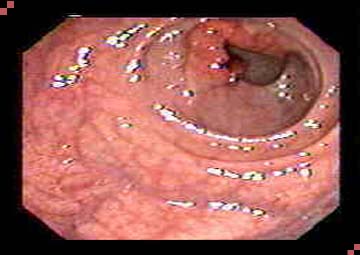

Hình ảnh trĩ nội độ 1

- Trong ống hậu môn có búi trĩ: Các búi trĩ nằm dọc trên đường lược phía bên trong ống hậu môn. Tuy chỉ nhỏ vừa bằng hạt gạo hoặc hạt đỗ nhưng tốc độ phát triển là rất nhanh.